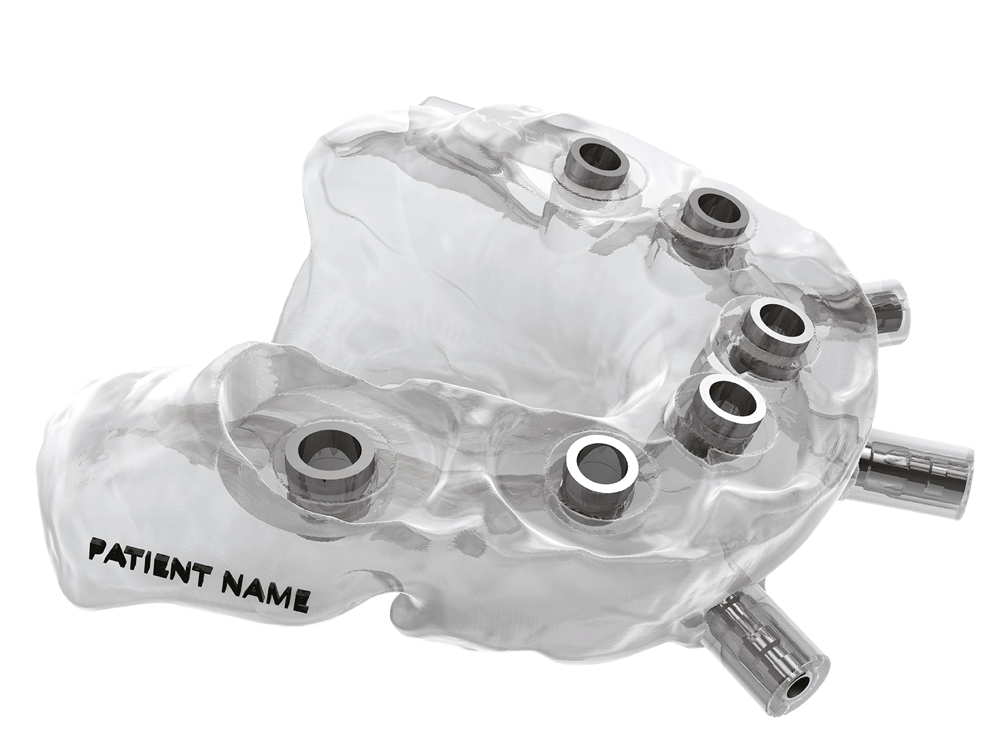

Realizzazione della dima chirurgica